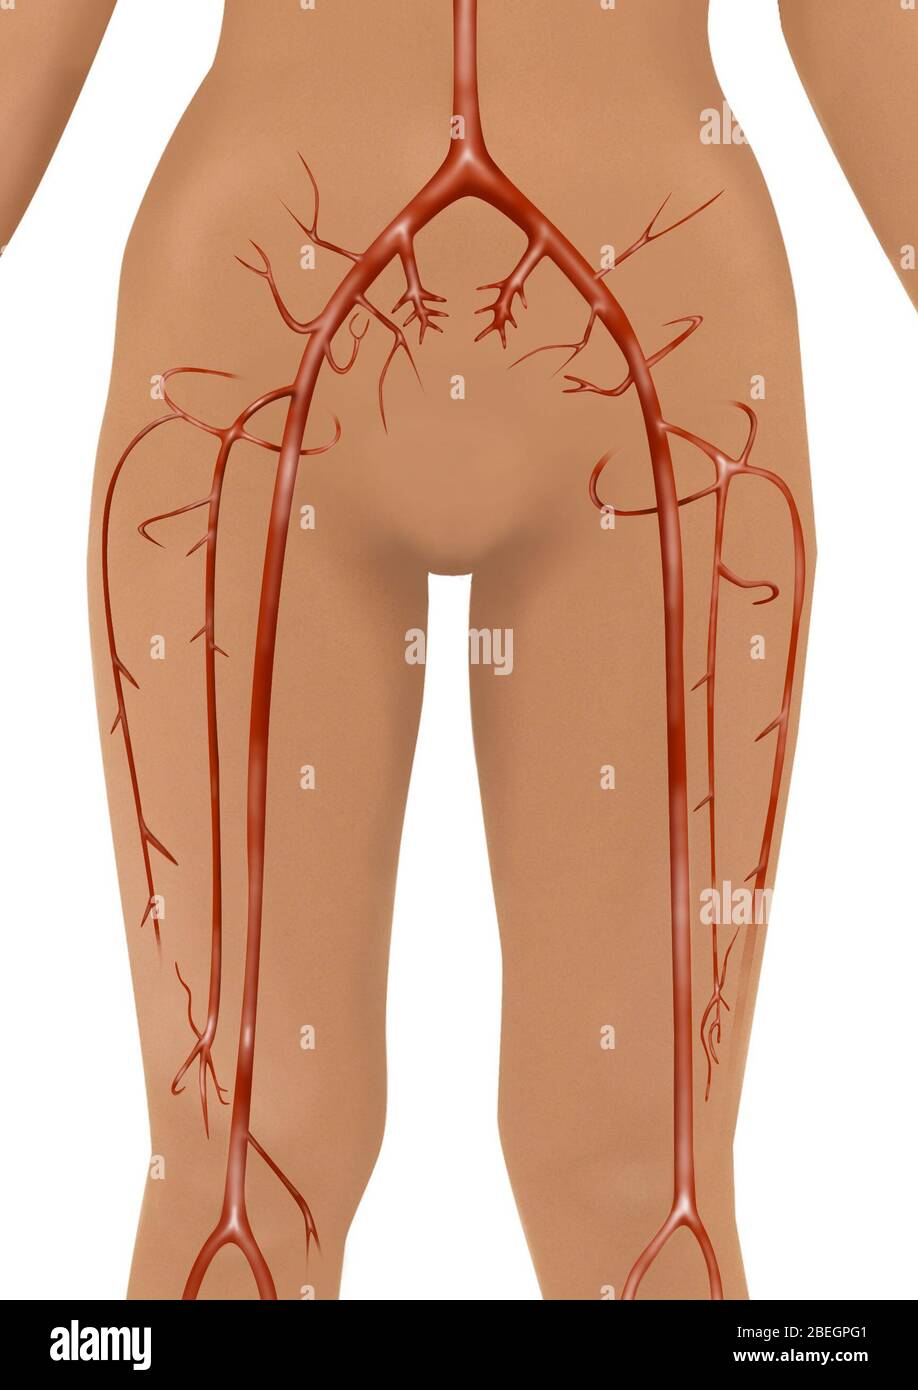

Artères Banque D'Imageshttps://www.alamyimages.fr/image-license-details/?v=1https://www.alamyimages.fr/arteres-image353181469.html

Artères Banque D'Imageshttps://www.alamyimages.fr/image-license-details/?v=1https://www.alamyimages.fr/arteres-image353181469.htmlRF2BEGPFW–Artères

Artères Banque D'Imageshttps://www.alamyimages.fr/image-license-details/?v=1https://www.alamyimages.fr/arteres-image353181473.html

Artères Banque D'Imageshttps://www.alamyimages.fr/image-license-details/?v=1https://www.alamyimages.fr/arteres-image353181473.htmlRF2BEGPG1–Artères